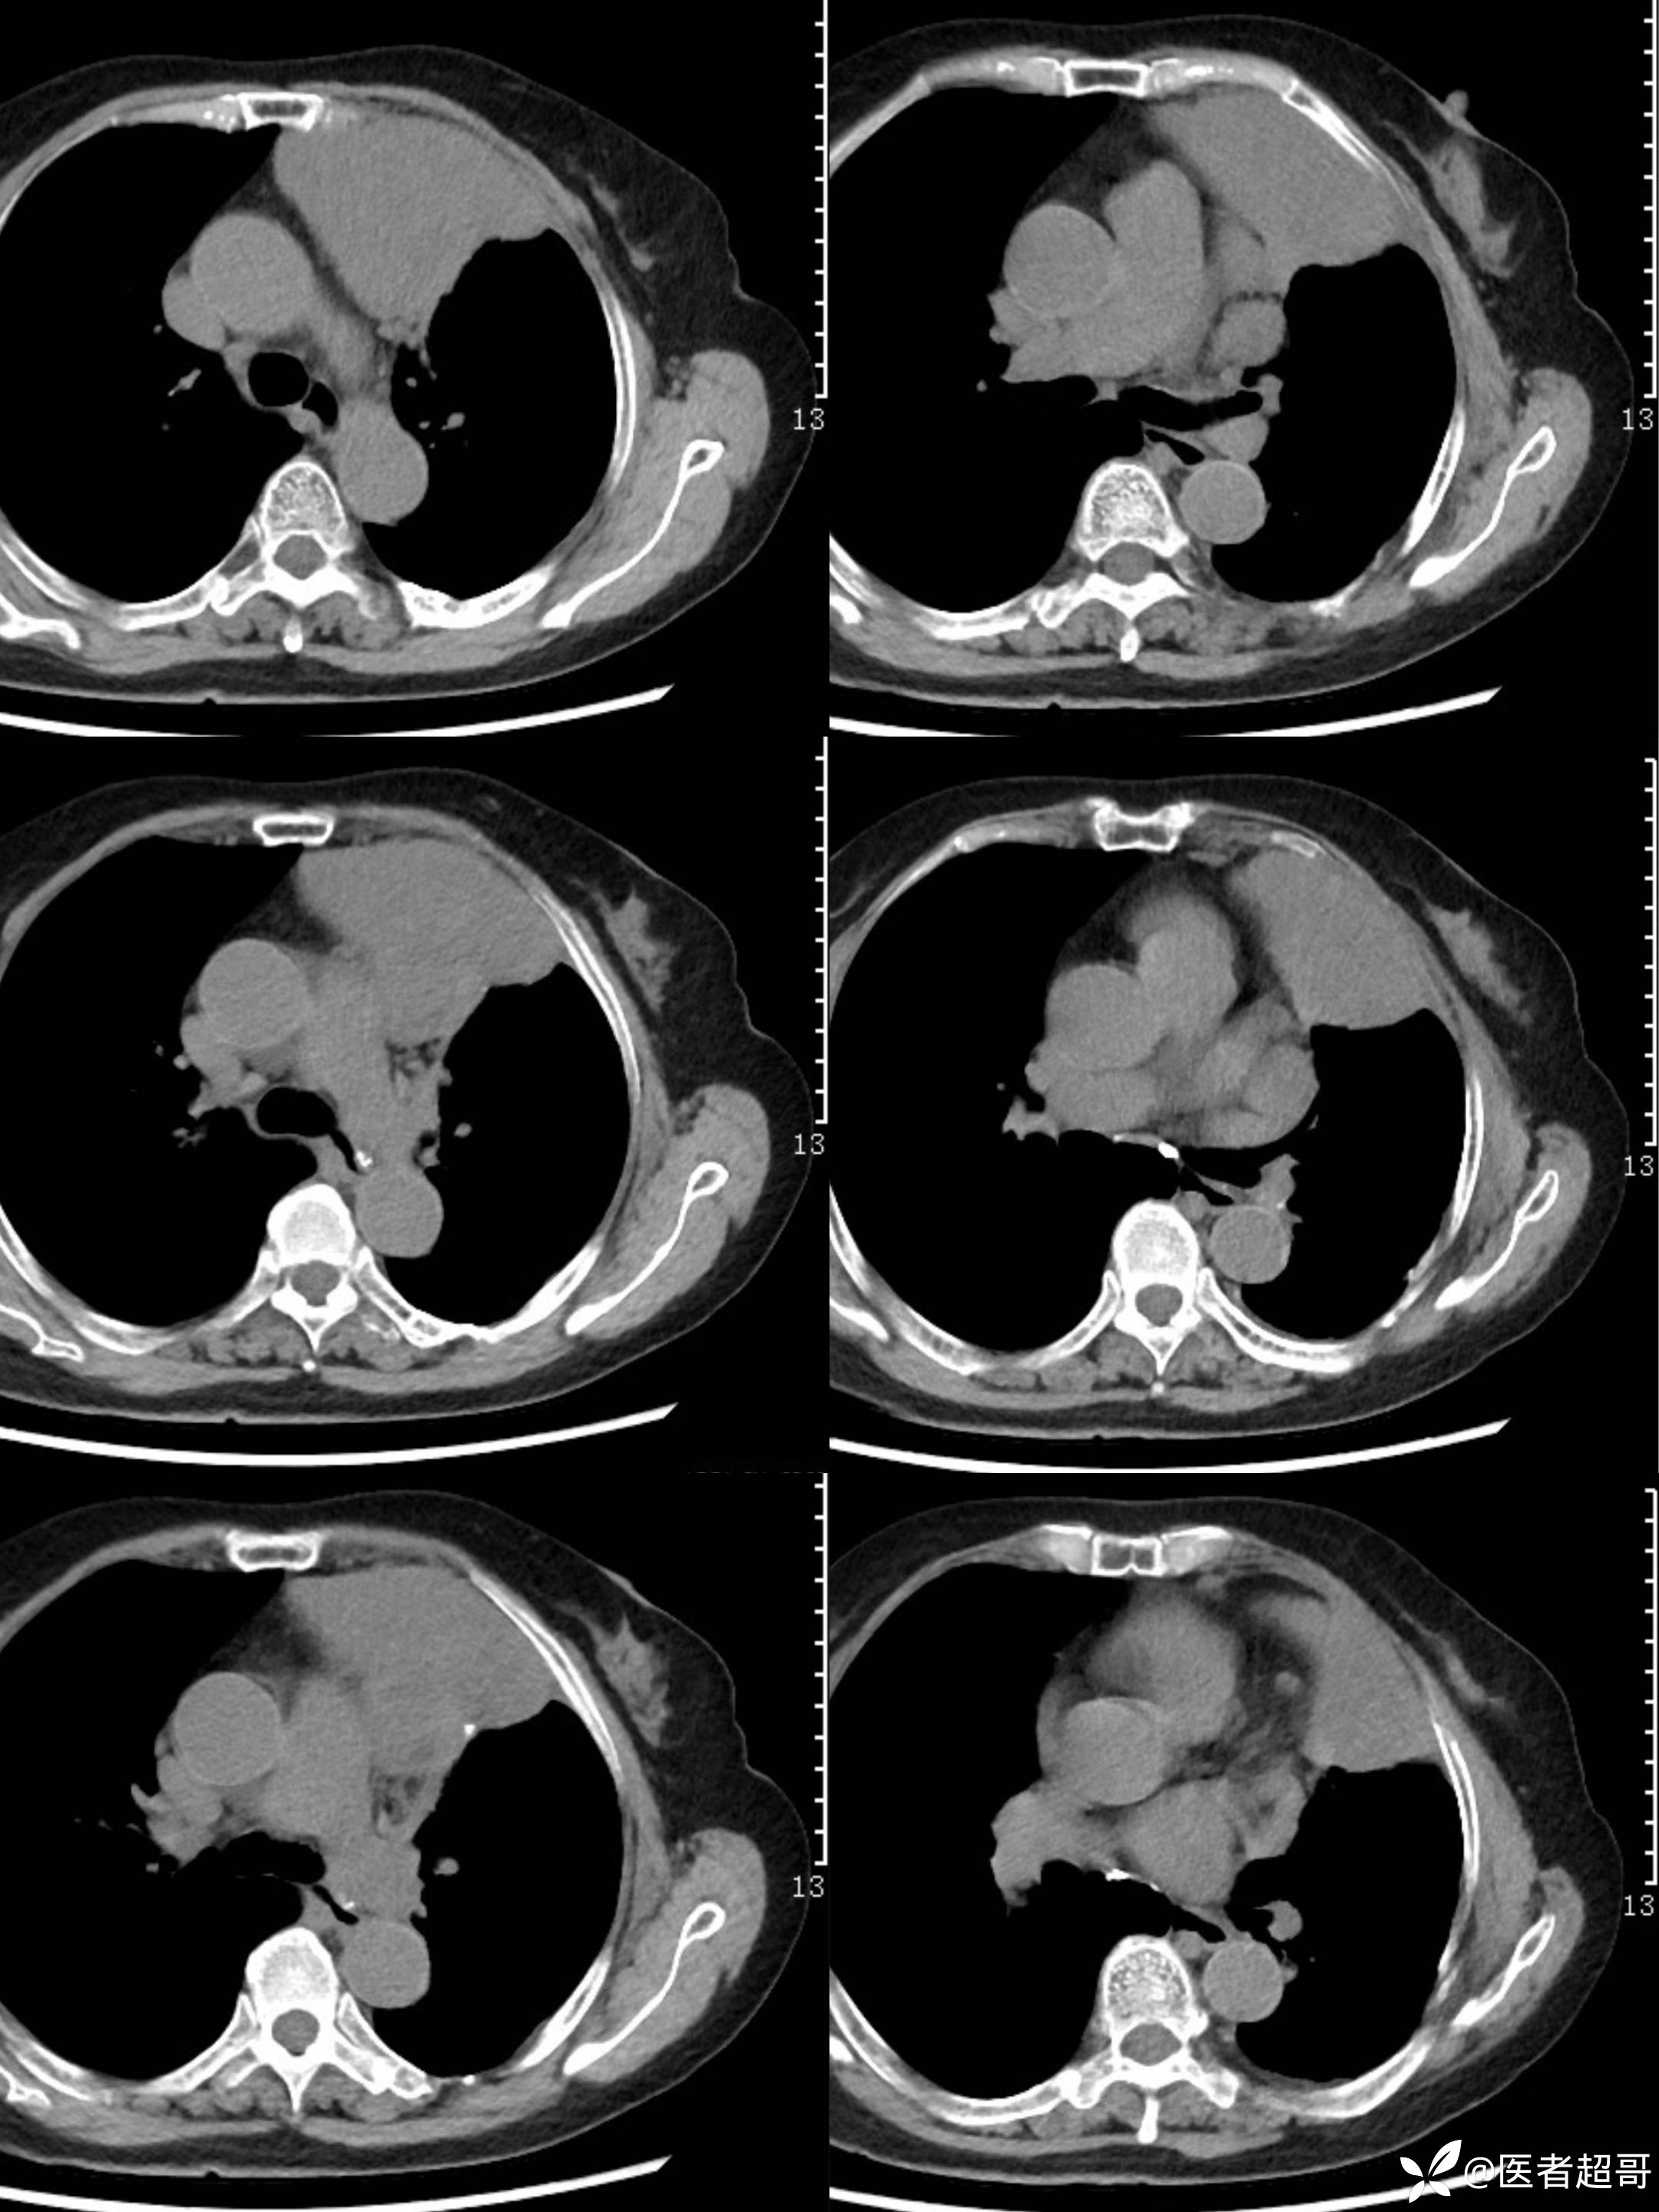

女73岁,体检发现左上纵隔占位1周

患者于1周前体检行CT检查提示:“左上纵隔见不规则团块状软组织密度影,大小约90*63mm”,患者平素偶有头晕,无明显胸闷气急,今为进一步治疗来我院就诊, 门诊以"左上纵隔肿物"收入院。

糖类抗原125(CA125):44.9(正常0-30.2),余实验室检查无殊